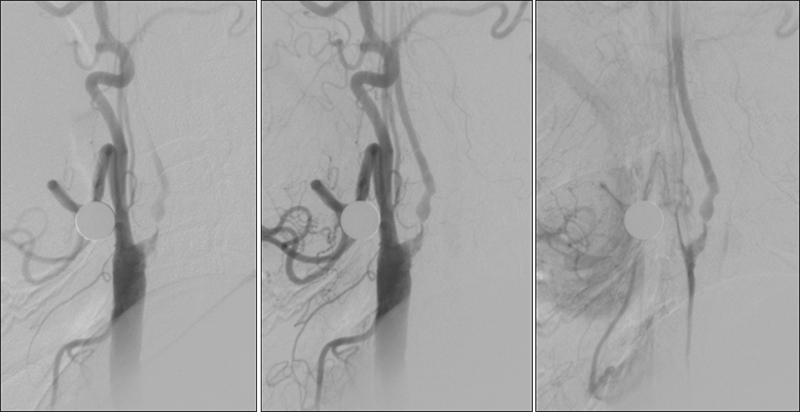

Εικόνα 1 και 2: Προσθιοπίσθια και πλάγια λήψη εγχύσεως στην αριστερή κοινή καρωτίδα. Εξεσημασμένη αθηρωματική στένωση (>95%) της εκφύσεως και του βολβού της αριστερής έσω καρωτίδος, με ελείμματα πληρώσεως (πρόσφατο θρομβωτικό υλικό). Η ροή υπεράνω της στενώσεως είναι ελαττωμένη και και καθυστερημένη.